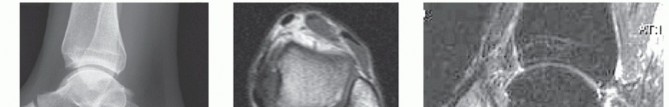

INDICATIONS Talar body avascular necrosis with collapse or infection ( FIG 1A ) is one indication for femoral…